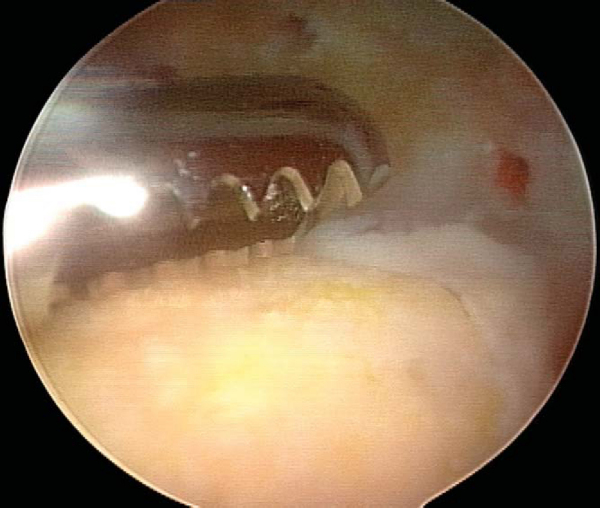

4. Microfracture of Lesion Bed with Further Débridement as Needed and Assessment of Fragment Reduction

A standard set of microfracture awls is used to penetrate the base of the lesion at 5-mm intervals. Inflow should be shut off after microfracture to confirm efflux of marrow elements from the base of the lesion (

Fig. 53-7

). If the process of microfracture generates an uneven surface that may impede congruent reduction, a small bur may be used to smooth the lesion bed. The osteochondral fragment is then reduced and held firmly in place with the elbow of a probe. Attention is given to the congruency of the reduction. Any step-off greater than 1 mm suggests the need for autogenous bone grafting to the bed of the lesion.

Figure 53-7   |